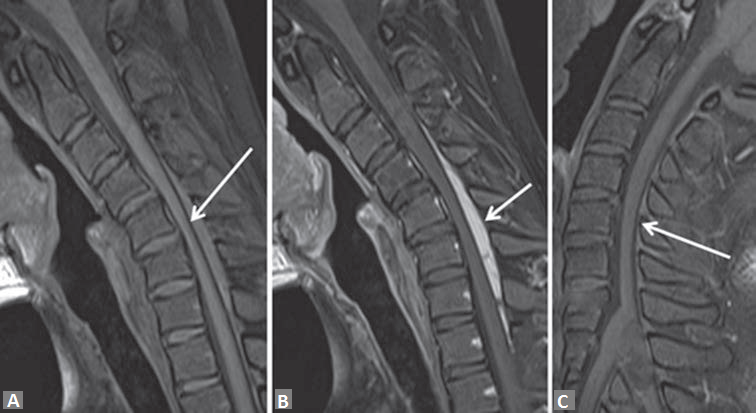

Given the young age of patient and focal spinal cord atrophy, a dynamic evaluation of the cervical spine with flexion and extension was performed. MRI during neck flexion on T2-weighted images [Figure 1b and c] revealed anterior displacement of the posterior dura with epidural flow voids and compression of the spinal cord. Flexion pre and postcontrast T1 MRI in midline sagittal plane [Figure 2a and b] revealed enhancement in posterior epidural space suggestive of enhancement of epidural plexus. Axial postcontrast T1 flexion MRI [Figure 3c and d] demonstrates thinning of the spinal cord, more prominent in right hemicord with posterior epidural enhancement. On extension in postcontrast T1 [Figure 2c], the posterior epidural space and its enhancement disappeared consequent to posterior displacement of posterior dura, also the cord compression was relieved.

Figure 2: T1-weighted sagittal noncontrast flexion (a) and dynamic pre and postcontrast flexion T1-weighted (b and c) magnetic resonance imaging reveals the anteriorly posterior dura (white arrow in a), enhancement in posterior epidural space (white arrow in b) suggestive of enhancement of epidural plexus. In postcontrast extension T1-weighted sagittal magnetic resonance imaging (c) the posterior epidural space and its enhancement disappeared consequent to posterior displacement of posterior dura, also the cord compression was relieved